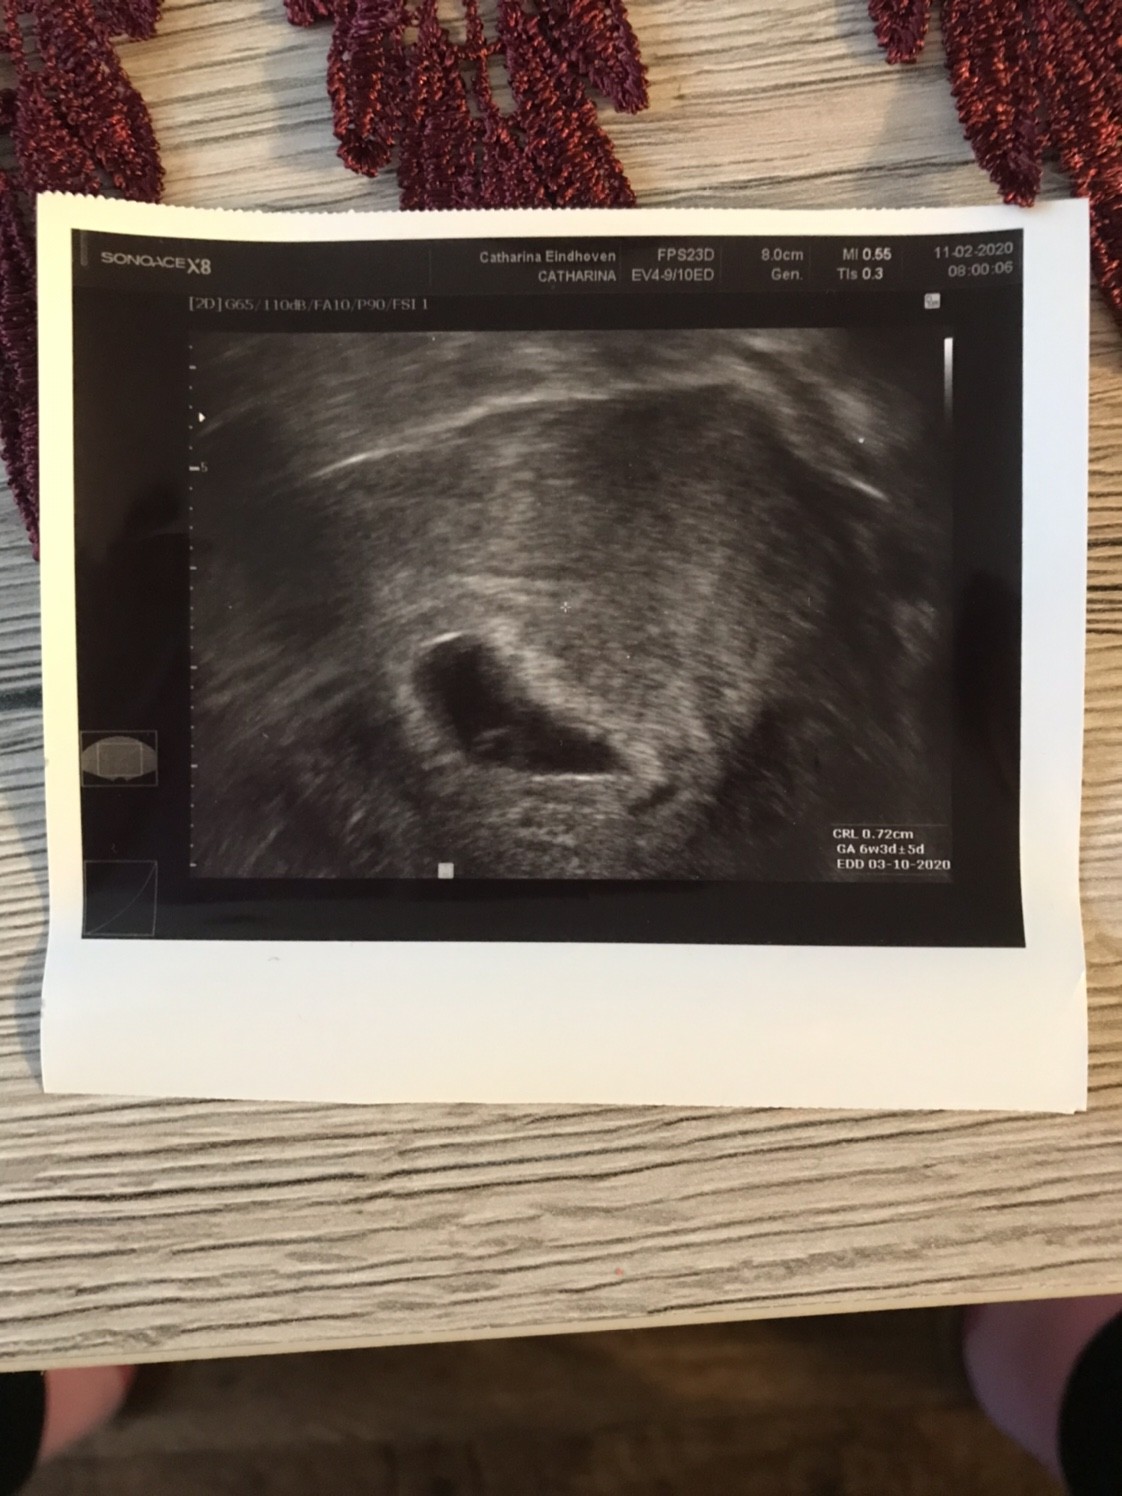

Nie martw się zaraz będzie serducho jak dzwonDziewczynki chciałabym Wam przedstawić mój zarodeczek, na razie nie ma serduszka - albo go nie widać, za tydzień (18.02) usg serduszkowe. Wg usg 6t3d czyli pokrywa się z wyliczeniami. Jestem szczęśliwa i spokojna.

Zobacz załącznik 1078812